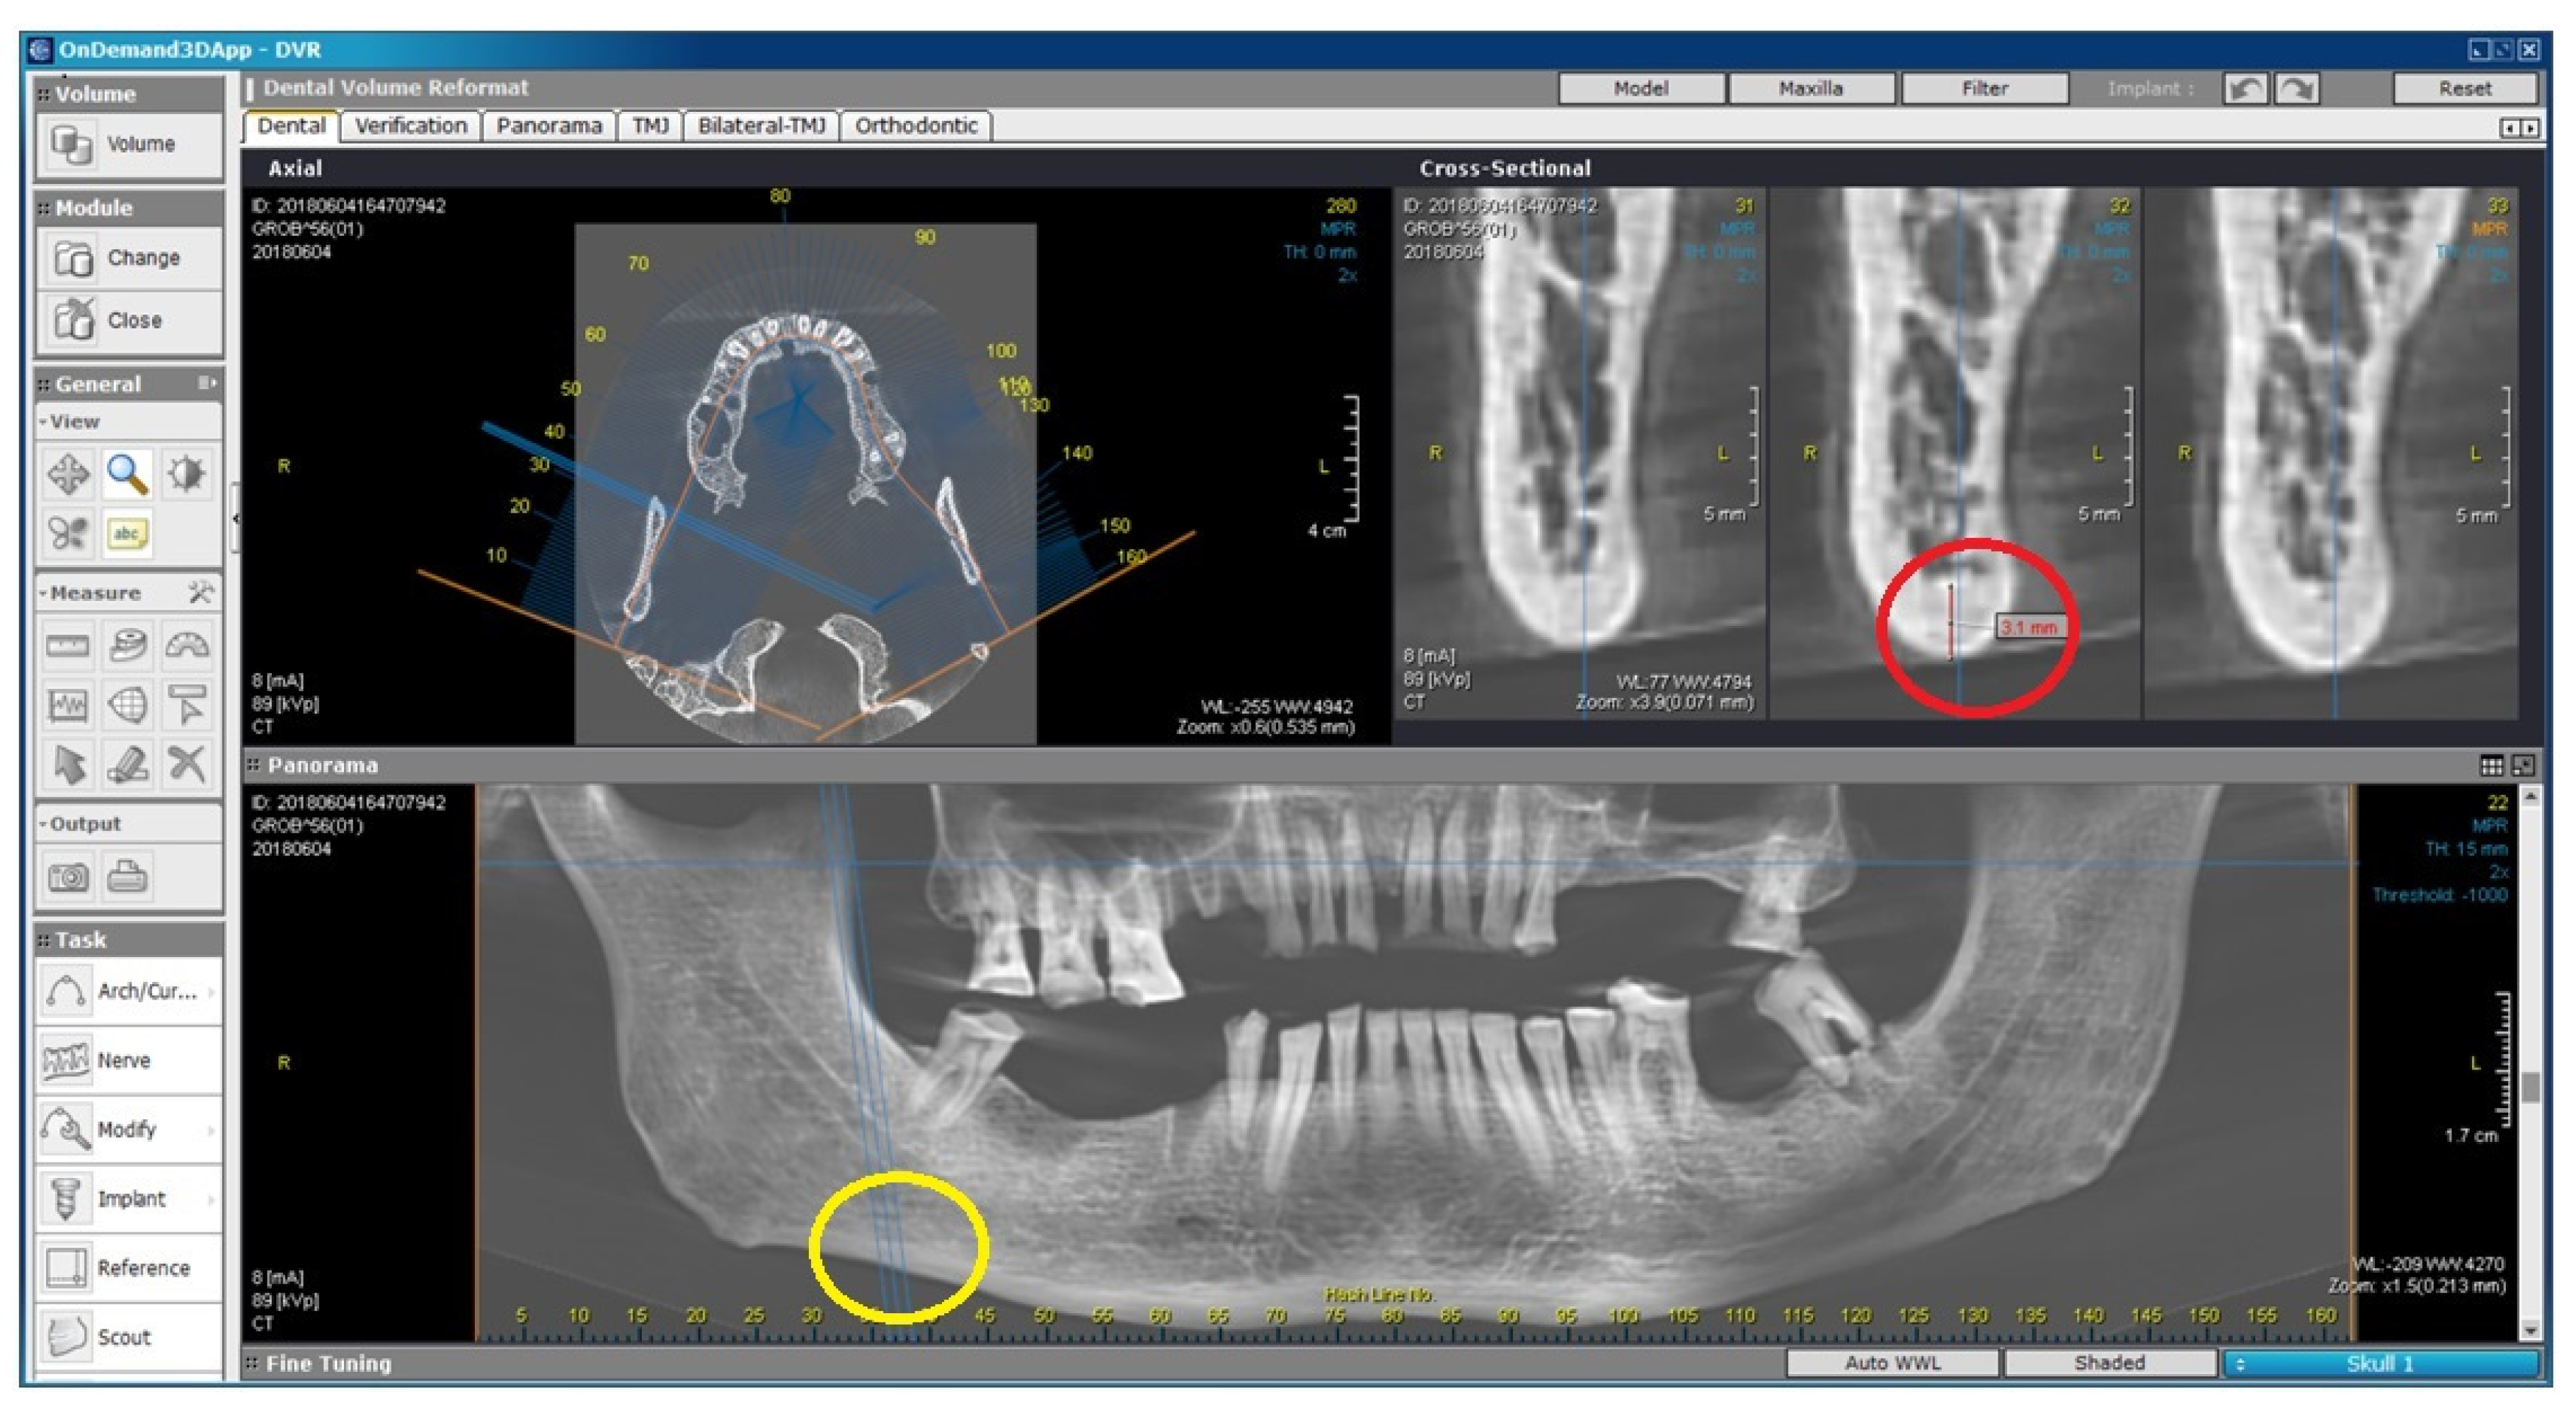

2.2. Radiomorphometric Assessments